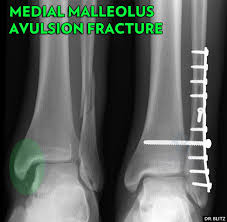

Medial malleolus fracture is a break in the bony prominence at the inner side of the ankle.

A trimalleolar fracture is a fracture of the ankle that involves the lateral malleolus, the medial malleolus, and the distal posterior aspect of the tibia, which can be termed the posterior malleolus. A lateral malleolus fracture is a fracture of the fibula. Fractures of the human ankles. Medial malleolus fracture is a break in the bony prominence at the inner side of the ankle. Case contributed by dr benoudina samir. Causes, symptoms, and diagnosis of bimalleolar fractures. Author reyus mammadli modified by july 26, 2018. Surgery on the medial malleoli can improve the chances of successful healing and allow the person to resume normal movement sooner. This article deals with the causes, symptoms, diagnosis, treatment and recovery time of medial malleolus fracture. However, only one case was worse than. 300 x 530 jpeg 55 кб. Fractures of the lateral malleolus are the most common type of ankle fracture. The lateral malleolus can fracture at a number of different.